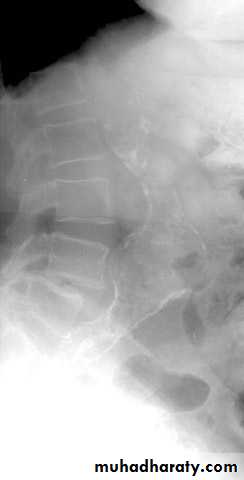

Plain Abdominal X-ray